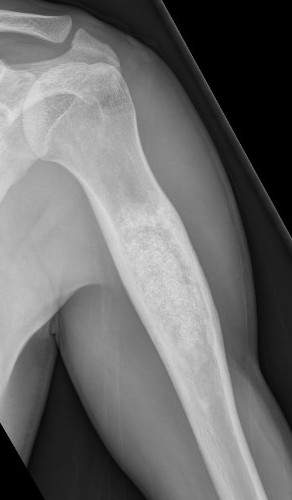

X-ray

Well-defined lucency

- thin sclerotic rim

- usually central

- thinned cortex with slight expansion

- thin internal septa

- can be multi-loculated

Fallen-Leaf (AKA fallen-fragment)

- with pathological fracture

- indicates that the lesion has no matrix and is fluid filled

Fallen leaf sign